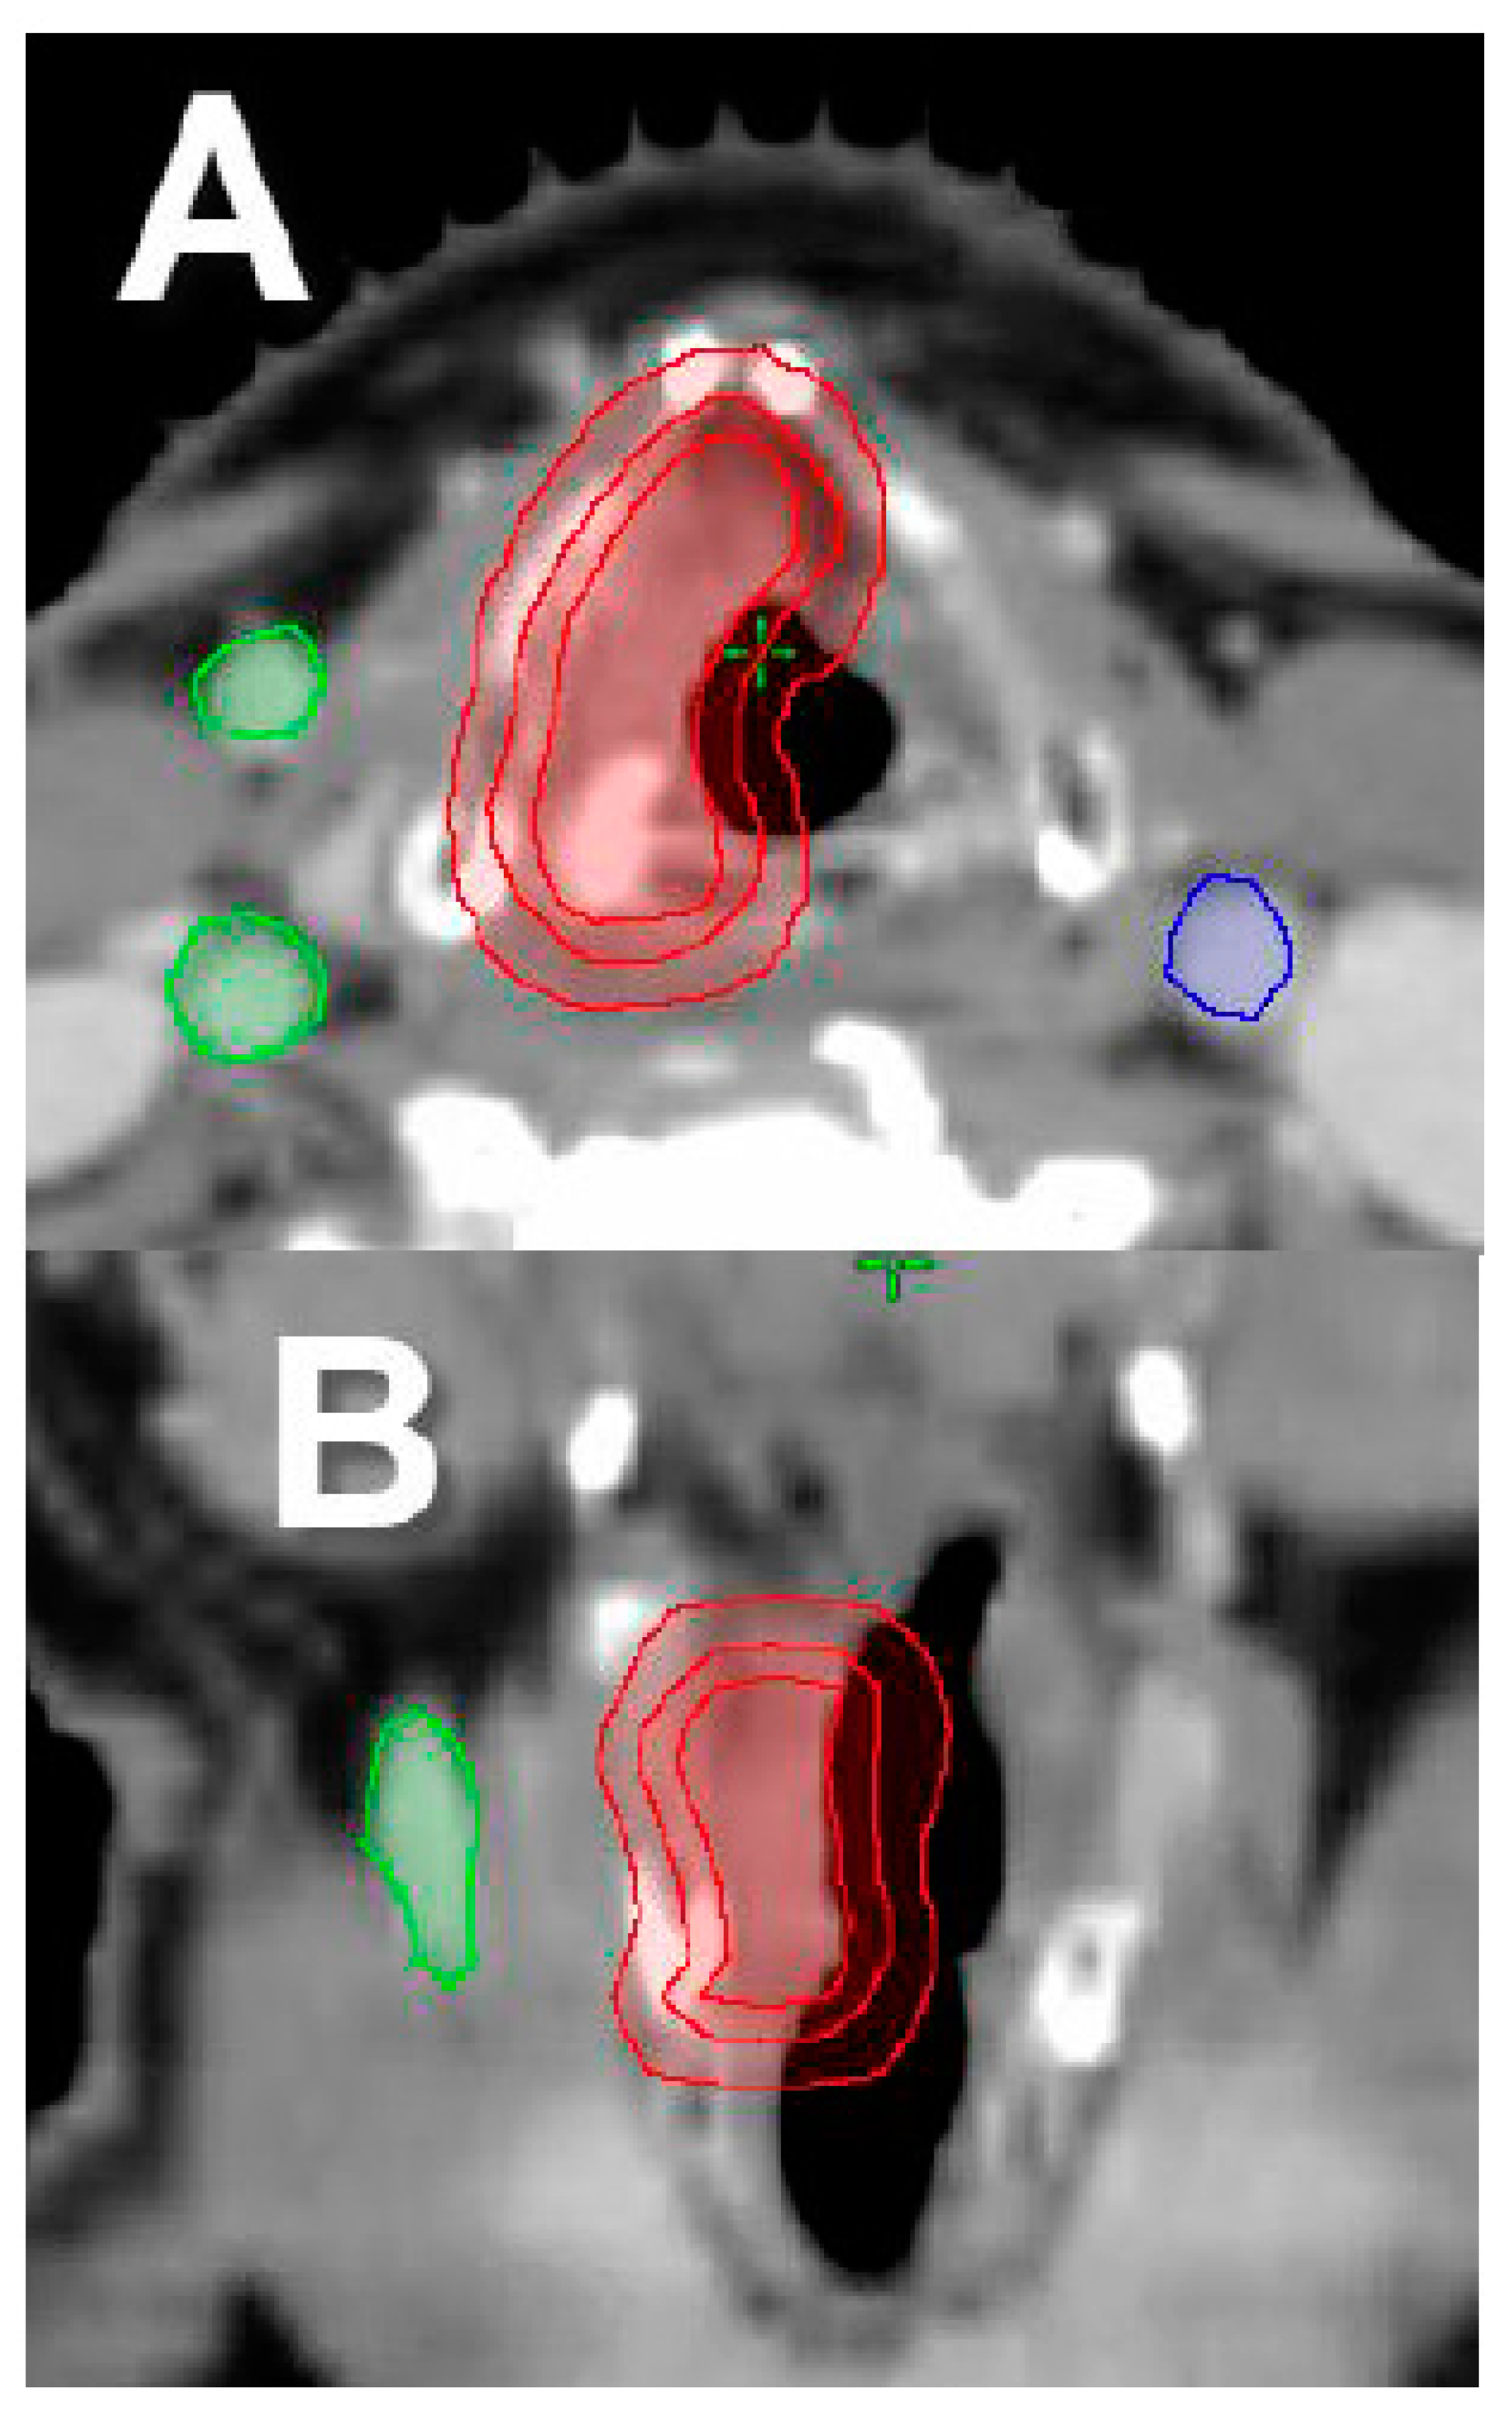

- Osman, S.O.; Astreinidou, E.; De Boer, H.C.; Keskin-Cambay, F.; Breedveld, S.; Voet, P.; Al-Mamgani, A.; Heijmen, B.J.M.; Levendag, P.C. IMRT for Image-guided single vocal cord irradiation. Int. J. Radiat. Oncol. Biol. Phys. 2012, 82, 989–997. [Google Scholar] [CrossRef] [PubMed][Green Version]

- Levendag, P.C.; Teguh, D.N.; Keskin-Cambay, F.; Al-Mamgani, A.; Van Rooij, P.; Astreinidou, E.; Kwa, S.L.S.; Heijmen, B.; Monserez, D.A.; Osman, S.O.S. Single vocal cord irradiation: A competitive treatment strategy in early glottic cancer. Radiother. Oncol. 2011, 101, 415–419. [Google Scholar] [CrossRef]

- Al-Mamgani, A.; Kwa, S.L.S.; Tans, L.; Moring, M.; Fransen, D.; Mehilal, R.; Verduijn, G.M.; Battenburg de Jong, R.J.; Heijmen, B.J.M.; Levendag, P.C. Single vocal cord irradiation: Image guided intensity modulated hypofractionated radiation therapy for T1a glottic cancer: Early clinical results. Int. J. Radiat. Oncol. Biol. Phys. 2015, 93, 337–343. [Google Scholar] [CrossRef]